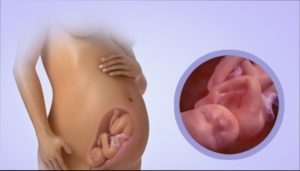

Вес ребенка на 37 неделе беременности составляет порядка 2,8-3,2 кг, а его рост достигает 47-49 см. Животик и головка малыша приблизительно одинаковы по окружности. Размеры плода уже полностью соответствуют тем, что имеет большинство новорожденных.

Его размер достигает уже 48-50 см и каждую неделю увеличивается в среднем на 1 см, а вес доходит до 2 900 г. Конечно, в этом смысле все младенцы разные.

На 37 неделе беременности малыш продолжает активно прибавлять в весе и теперь его масса составляет около 2900-3000 г., а длина в среднем 48-49 см. Ребенок уже полностью готов к появлению на свет!

Рост малыша в этот период 48–50 см, вес плода – 2,8–2,9 кг, как раз то, что мы привыкли видеть после появления младенцев на свет.